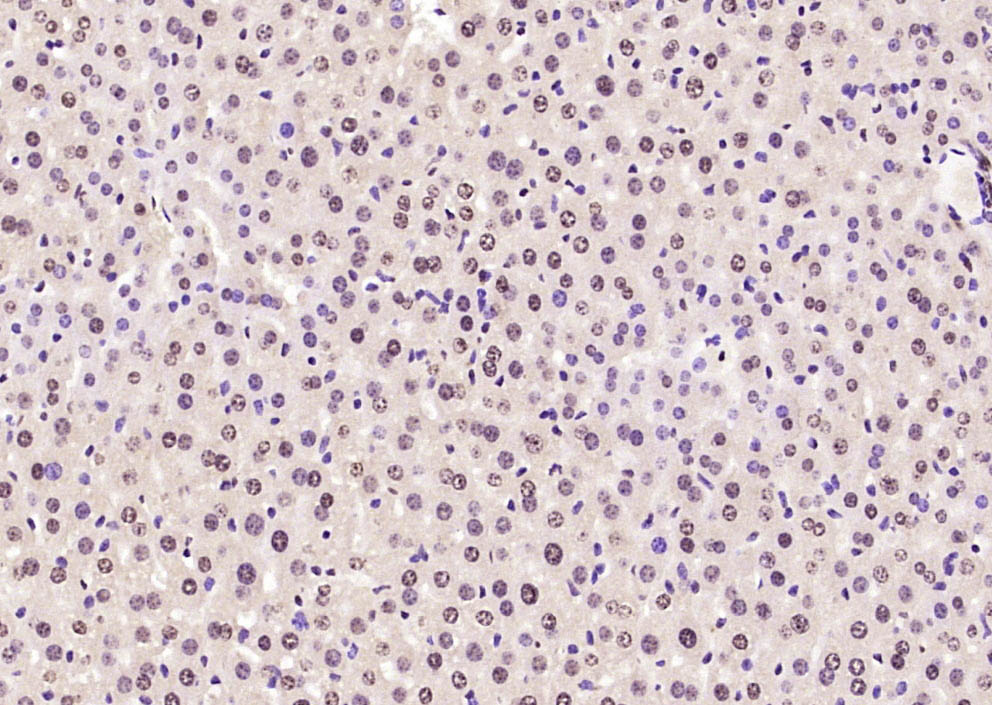

Paraformaldehyde-fixed, paraffin embedded Human colon cancer; Antigen retrieval by boiling in sodium citrate buffer (pH6.0) for 15min; Block endogenous peroxidase by 3% hydrogen peroxide for 20 minutes; Blocking buffer (normal goat serum) at 37°C for 30min; Antibody incubation with SOX9 Polyclonal Antibody, Unconjugated (bs-10725R) at 1:400 overnight at 4°C, DAB staining.